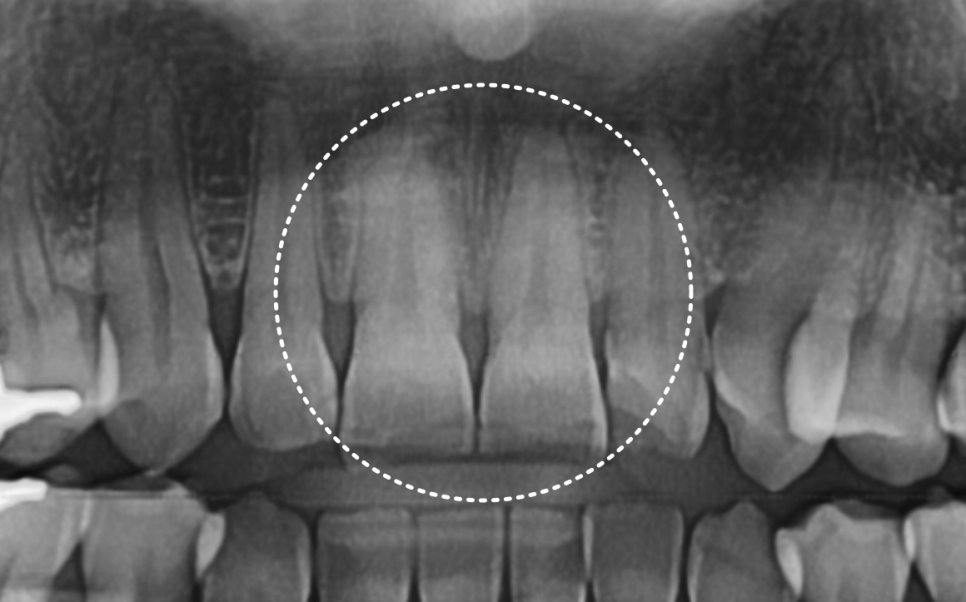

사진과 검사상 다행히도

신경이나 뿌리까지 금이 이어진 흔적은

보이지 않았습니다.

교합을 확인했을 때도

위 앞니가 아래 앞니를 살짝 덮는

정상 범주의 교합이어서,

레진으로 수복하더라도

쉽게 다시 깨질 가능성은 높지 않은 상태였습니다.